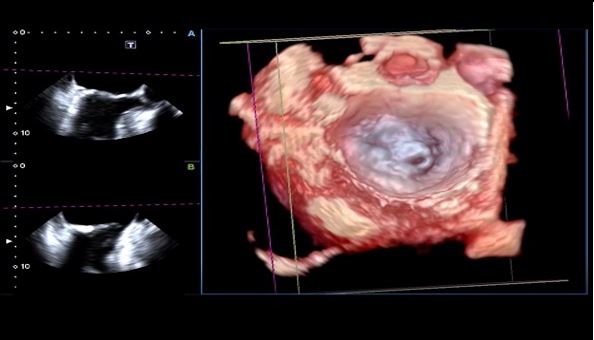

Аналіз мітрального клапана в 4D (4D MVA)

Цей унікальний інструмент забезпечує анатомічну та функціональну оцінку мітрального клапана, проводячи близько 40 вимірювань за 30 секунд, та допомогає лікарю при плануванні інтервенційного втручання, наприклад для операції транскатетерної імплантації мітрального клапана.

- Інтуїтивно-зрозумілий кольоровий 3D аналіз

- 4-віконний дисплей (обрані користувачем зрізи, різні площини сканування, 3D-реконструкція)

- Реконструкція мітрального клапана візуалізує форму стулок клапана, що допомагає оцінити пролапс або деформацію.